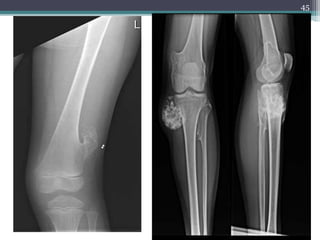

Osteochondroma.

Hard, smooth, nodular swelling of the distal

femur, skin and soft tissues are easily movable

and the knee joint is freely mobile.